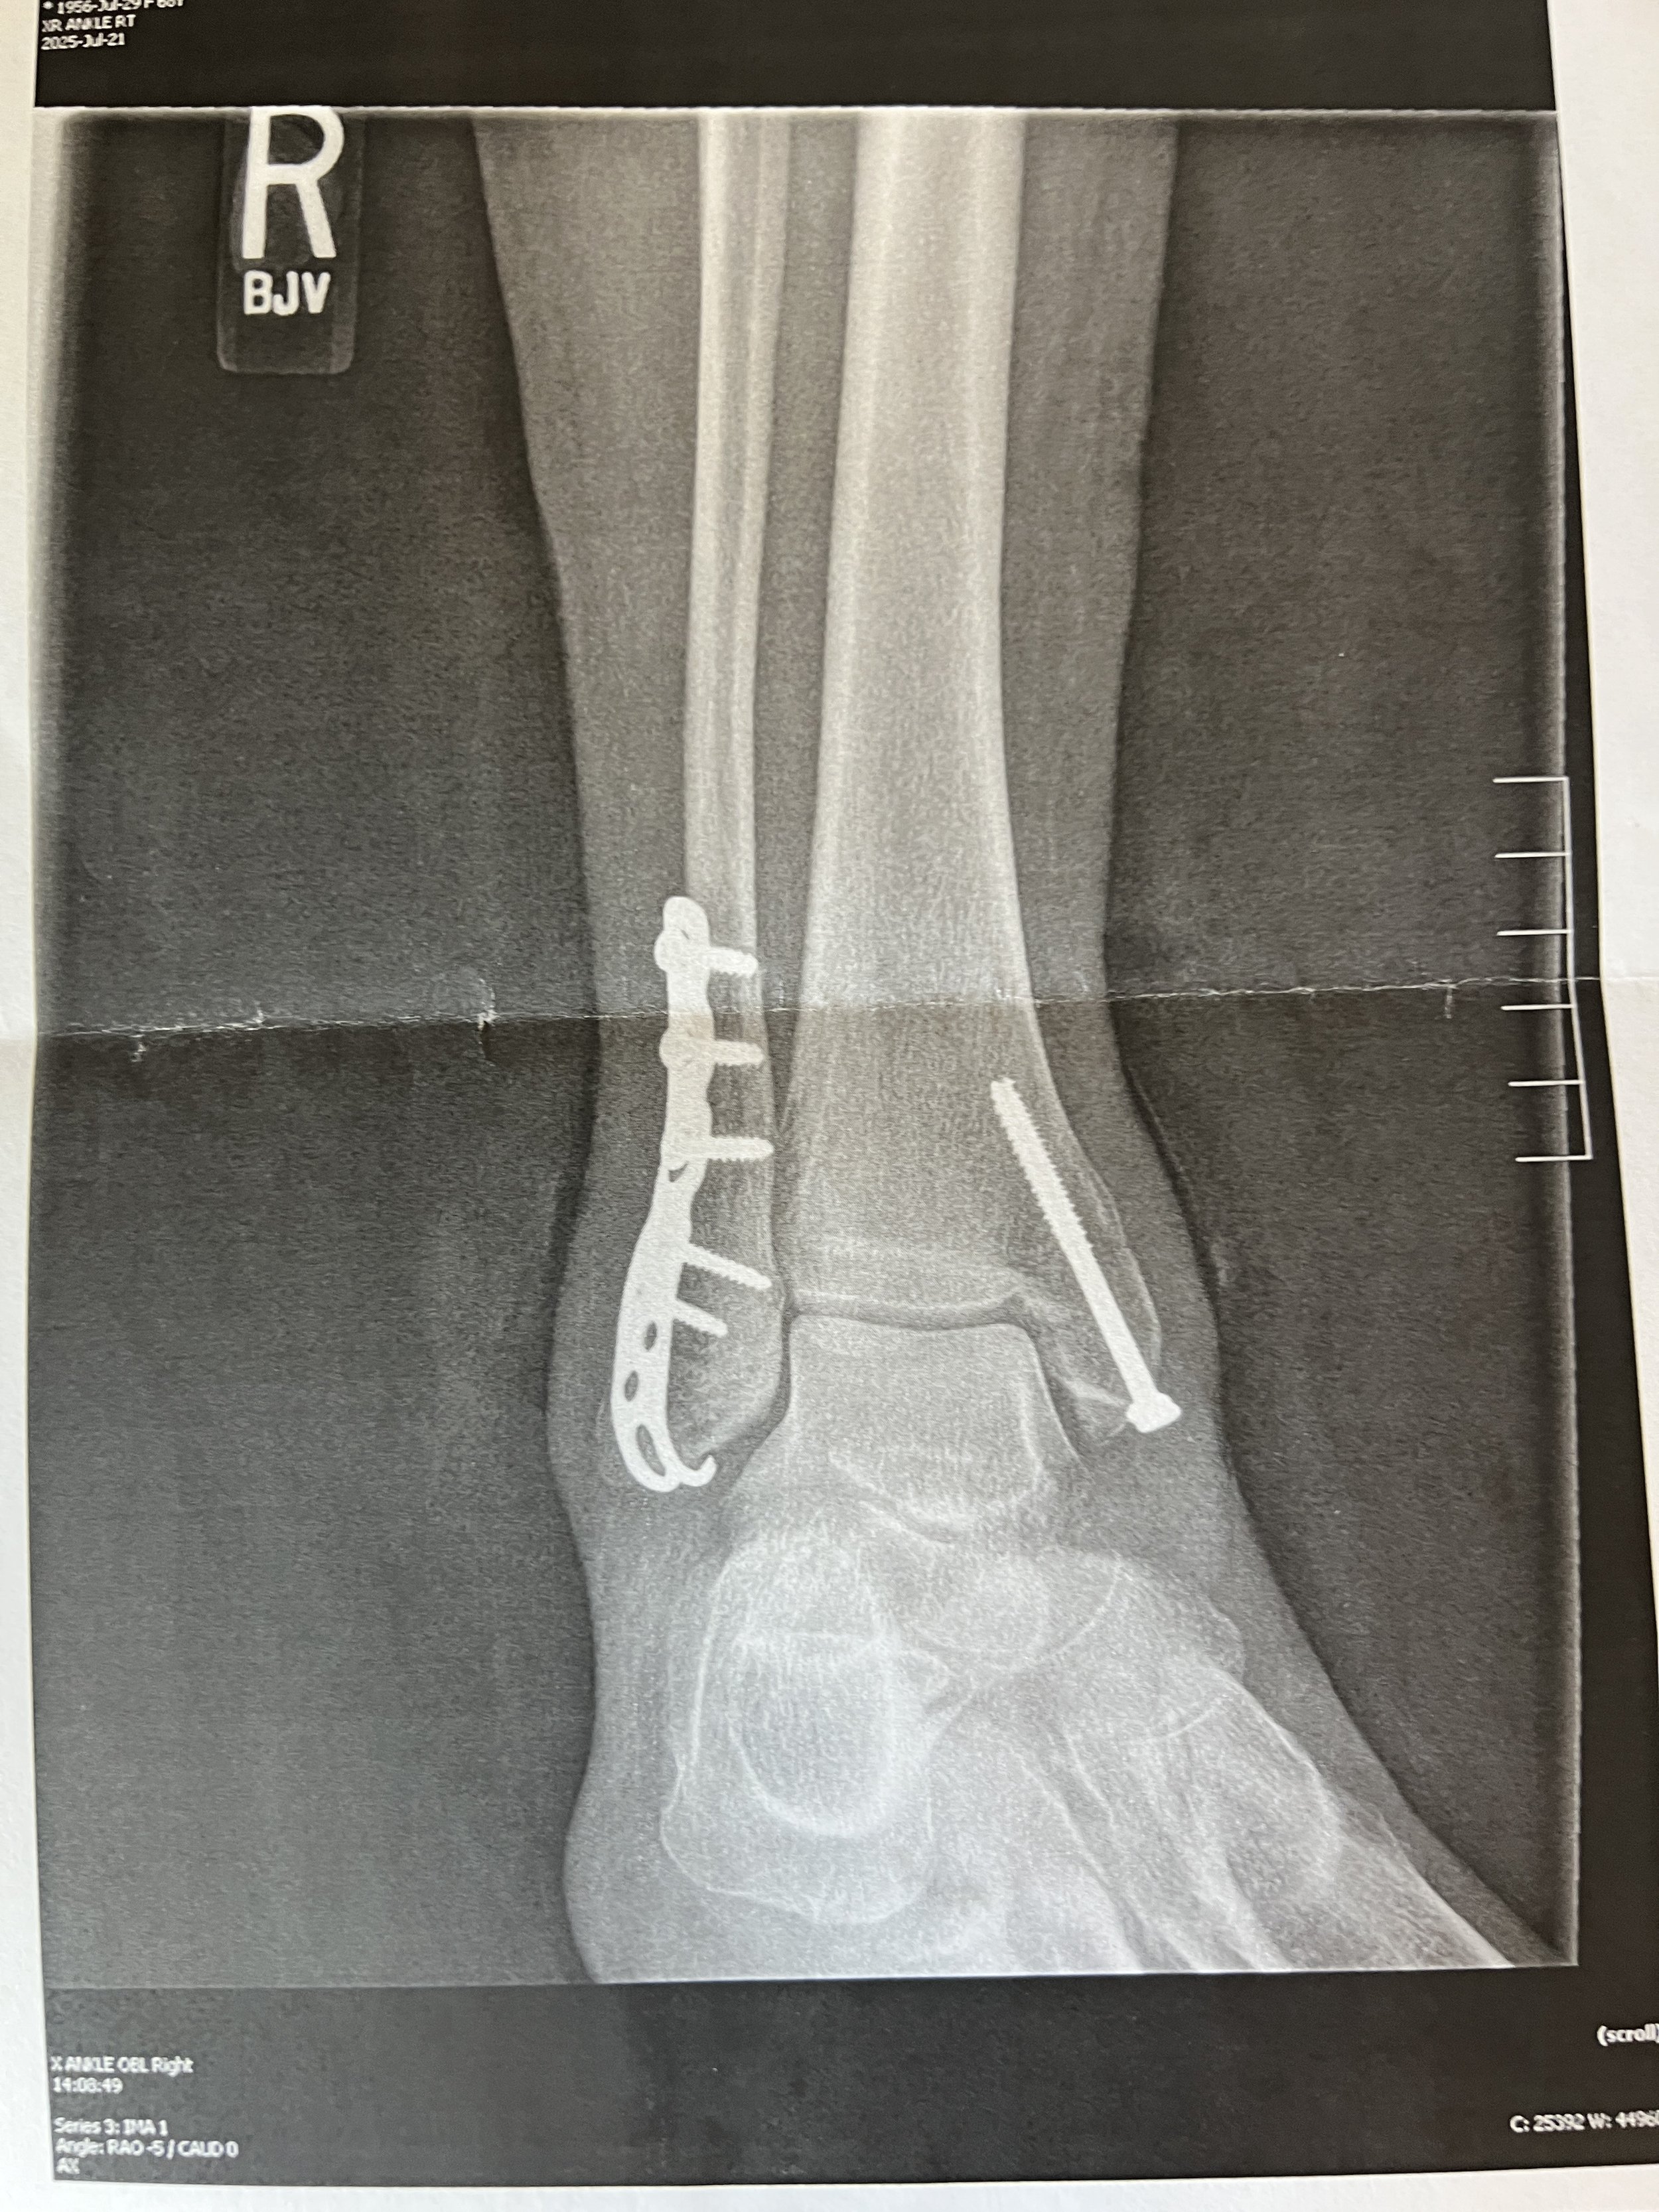

my two week post op ankle X-ray after ORIF surgery

This is an X-ray of my ankle, two weeks post op, after an ORIF surgery for a bimalleolar fracture and a ruptured tendon.

It turned out I had a bimalleolar fracture along with a ruptured peroneal tendon and torn ligaments.